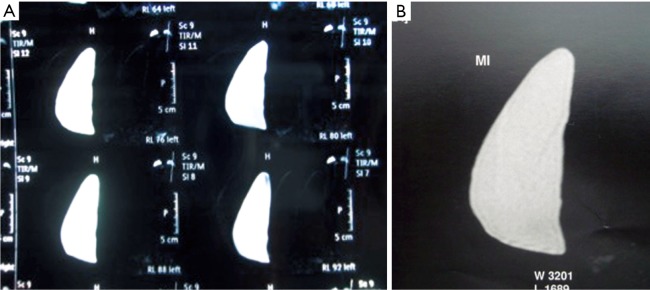

High cohesive gel anatomical implants maintain shape in vivo, with the possibility of checking it by MRI studies (Figure 7).

Figure 7.

CT scan: anatomical implant keeping the shape in vivo.